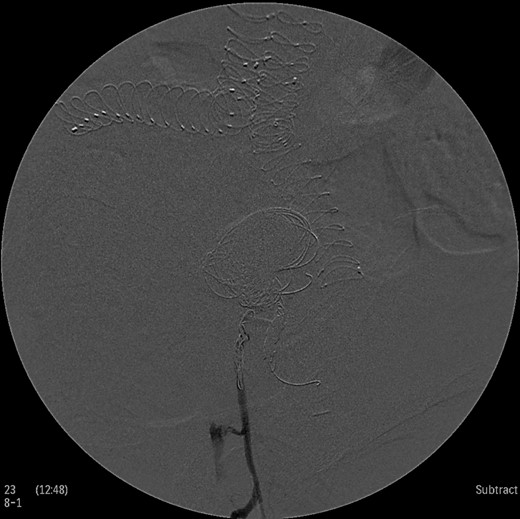

Under general anesthesia the patient was placed in prone position and a 15 cm transverse incision, slightly curvy was performed in the middle part of the right gluteal region between the posterior superior iliac spine and ischiac tuberosity. The gluteus maximus muscle was split and the inferior gluteal artery was identified as it entered the gluteal region through the greater schiatic foramen near the schiatic nerve below the piriformis muscle. The inferior gluteal artery was punctured using Seldinger technique and a 4Fr was introduced into the artery (Fig. 2). An angiography was made revealing the aneurysm of the right IIA and two feeding arteries, inferior gluteal artery and probably a branch of superior gluteal artery, filling the sac (Fig. 3). A 0.014 inch Pilot guide wire (Boston Scientific Corporation, USA) was inserted into the aneurysm and a microcatheter 3 Fr RENEGADE STC (Boston Scientific Corporation, USA) was advanced over the wire. After removing the wire, embolization microcoils (Interlock, Boston Scientific, USA) (two coils 22–600 mm, two coils 20–500 mm, three coils 18–500 mm) were introduced into the aneurysm sac (Fig. 4). A 5 Fr sheath was subsequently placed, a 5Fr RIM catheter (Cordis, USA) was advanced to the aneurysm sac through a 0.035 inch Terumo guide wire (Glidewire, Terumo Corporation, Japan) and selective catheterization of the second feeding artery was performed (Fig. 5). Embolization coils (Interlock, Boston Scientific, USA) were inserted into the two feeding arteries (two coils 15–400 mm) (Fig. 6). Completion angiogram depicted absence of blood flow into the aneurysm and the runoff vessels (Fig. 7). The patient had an uneventful recovery period without buttock claudication, ischemic complications and discharged in good condition. A follow-up CT aortography after 6 months depicted complete thrombosis of the aneurysm (Fig. 8).

Intraoperative angiogram showing the presence of the aneurysm and two collateral vessels, embolization with coils of the sac and two feeding arteries. Completion angiogram depicted absence of blood flow in the IIA aneurysm and the runoff arteries.